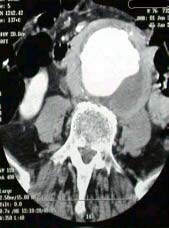

Imagem (Aneurisma abdominal da aorta)

Tomografia Computadorizada: é o teste mais preciso para fazer uma imagem de aneurisma aórtico. Demonstra claramente o tamanho e a extensão do aneurisma aórtico e sua relação com as artérias renais e ilíacas.

Imagem (Tomografia computadorizada)